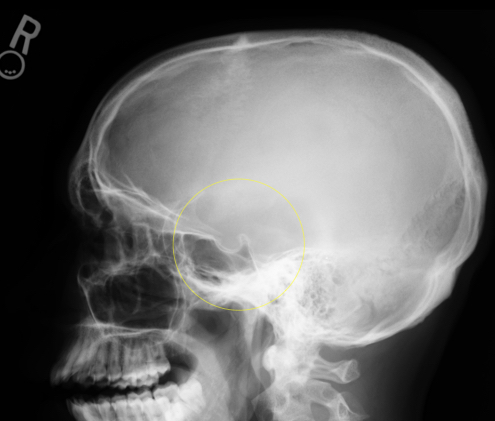

The sella turcica should be seen in profile and not rotated. The mandibular condyles should be superimposed.

Sella Turcica

The sella turcica is a deep depression on the superior surface of the sphenoid bone of the skull. It houses and protects the pituitary gland, which is an endocrine gland that controls many of the hormones within our bodies.

The sella turcica lies in the midsagittal plane of the cranium at a point ¾ inch anterior and ¾ inch superior to the EAM.

Sella Turcica Anatomy